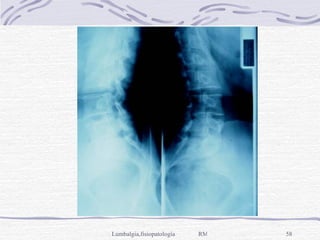

Diagnóstico Laboratorio: B.H., E.G.O., Q.S., perfil reumatológico Por imagen, Rx simple de columna lumbar AP, Lateral y Oblicua y Ap de Pelvis, con el paciente de pie y descalzo. TAC y RM en situaciones más específicas

Diagnóstico Laboratorio: B.H.,E.G.O., Q.S., perfil reumatológico Por imagen, Rx simple de columna lumbar AP, Lateral y Oblicua y Ap de Pelvis, con el paciente de pie y descalzo. TAC y RM en situaciones más específicas